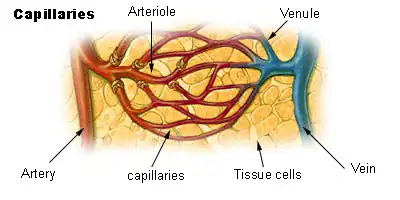

Blood Flow After the Heart

Aorta-Arteries-Arterioles-Capillaries-Venules-Veins-Vena Cava

Blood Flow Through Capillaries

From the arterioles, the blood then enters one or more capillaries. The walls of capillaries are so thin and fragile that blood cells can only pass in single file. Inside the capillaries, exchange of oxygen and carbon dioxide takes place. Red blood cells inside the capillary releases their oxygen which passes through the wall and into the surrounding tissue. The tissue then releases waste, such as carbon dioxide, which then passes through the wall and into the red blood cells.

Arteries

Arterioles

An arteriole is a small artery that extends and leads to capillaries. Arterioles have thick smooth muscular walls. These smooth muscles are able to contract (causing vessel constriction) and relax (causing vessel dilation). This contracting and relaxing affects blood pressure; the higher number of vessels dilated, the lower blood pressure will be. Arterioles are just visible to the naked eye.

Capillaries

Capillaries are the smallest of a body’s vessels; they connect arteries and veins, and most closely interact with tissues. They are very prevalent in the body; total surface area is about 6,300 square meters. Because of this, no cell is very far from a capillary, no more than 50 micrometers away. The walls of capillaries are composed of a single layer of cells, the endothelium, which is the inner lining of all the vessels. This layer is so thin that molecules such as oxygen, water and lipids can pass through them by diffusion and enter the tissues. Waste products such as carbon dioxide and urea can diffuse back into the blood to be carried away for removal from the body.

The "capillary bed" is the network of capillaries present throughout the body. These beds are able to be “opened” and “closed” at any given time, according to need. This process is called autoregulation and capillary beds usually carry no more than 25% of the amount of blood it could hold at any time. The more metabolically active the cells, the more capillaries it will require to supply nutrients.

Venules

A venule is a small vein that allows deoxygenated blood to return from the capillary beds to the larger blood veins, except in the pulmonary circuit where the blood is oxygenated. Venules have three layers; they have the same makeup as arteries with less smooth muscle, making them thinner.